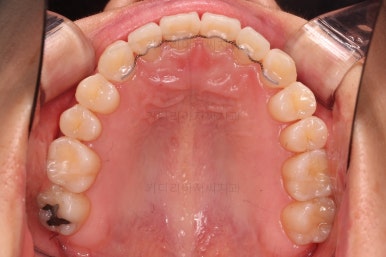

4. 마무리

철사교정과 마찬가지로 앞니쪽에 유지장치를 구성하고 치료를 종료합니다.

매우 가지런해졌고요.

맞물림도 좋아졌고, 중앙선도 잘 맞춰졌습니다.

부산인비절라인 전후 비교해 보겠습니다.

입매를 유지하면서 비발치이더라도 입이 더 나오지 않게 마무리 했고요.

가지런한 느낌 좋고, 중앙선이라던지 교합도 좋아졌습니다.